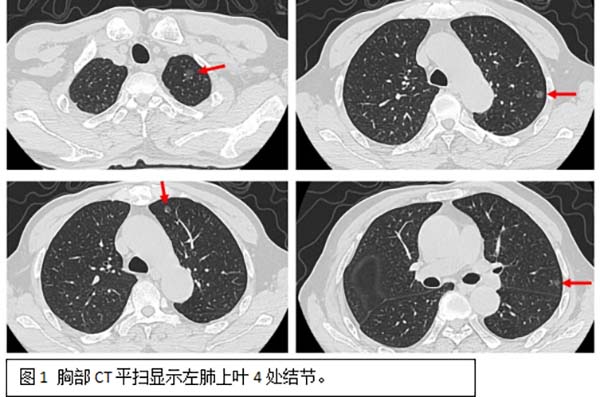

面对如此复杂的病情,胸外一科主任阮军忠带领团队与CT介入科主任王东坡团队进行了深入的术前讨论和准备,患者肺部存在的6个高危结节,直径均在6-10mm之间,分别位于左肺上叶尖后段、前段(图1)及左肺下叶背段(图2),若全部通过外科手术切除,不仅难以准确定位所有结节,还可能需要切除超过一半的左侧肺组织,对患者的生活质量和手术风险都构成严峻挑战。